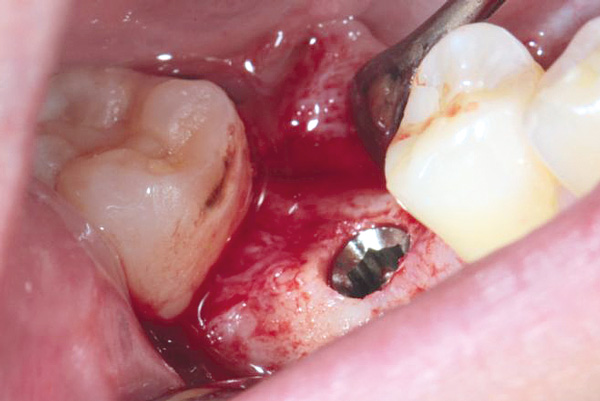

Situation after tooth extraction.